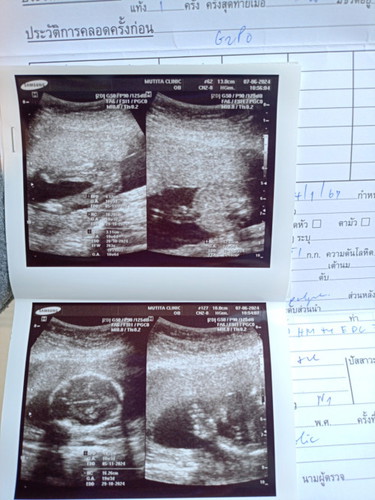

หมอบอกได้ลูกสาวค้า

ภาพที่2เเฟนจำไม่ได้คือไรไช่หัวไหมค่ะเเม่ๆ5555เรามองม่เห็นเลยตอนหมอซาว555

ภาพที่2หัวกระโหลก ภาพแรก อวัยวะเพศหญิงชัดเจนคะ ของบ้านนี้เห็นหน้าน้องแล้วก็อวัยวะเพศชายชัดเจนคะ